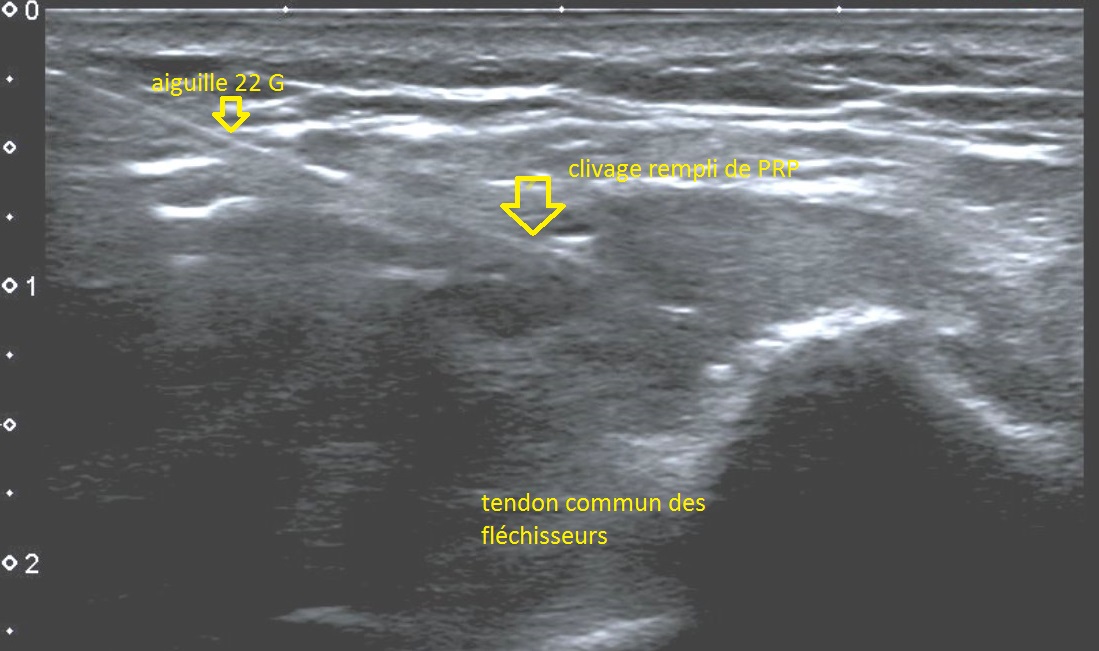

L'injection de PRP est réalisée sous contrôle échographique avec un matériel de dernière génération (Toshiba Aplio 500) et des sondes linéaires de haute fréquence adaptées à la pratique de la radiologie interventionnelle.

Une anesthésie locale peut être réalisée mais n'est pas obligatoire. Par contre, le produit anesthésiant ne doit pas être mélangé ou injecté à proximité des facteurs plaquettaires (risque d'inhibition) et doit se faire en périphérie du tendon. Ensuite, l'aiguille est placée au sein de la fissure. Le PRP est injecté sous contrôle échographique. Les consignes d'usage habituelles (repos, surveillance) sont ensuite données au patient.